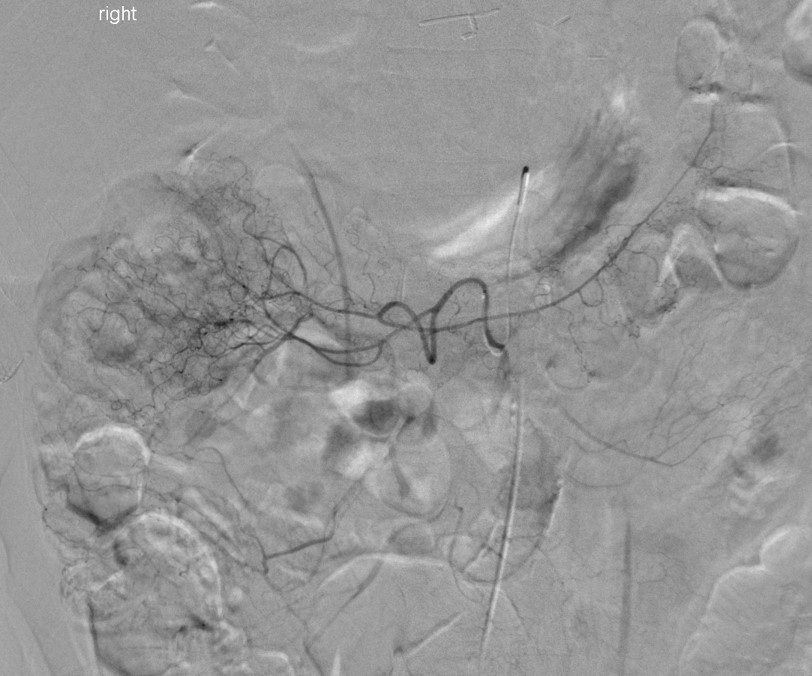

polyarteritis nodosa(PAN)

multiple small aneurysms in the right renal arterioles

this is an Aunt Minnie and diagnostic of PAN

associated with HBV and HCV